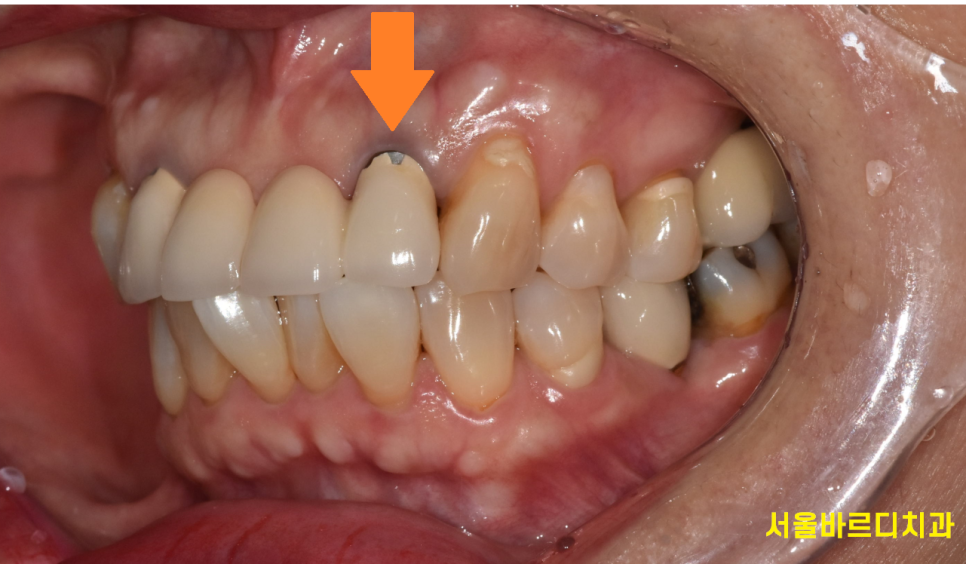

240719

지르코니아 보철로 앞니를 교체하였습니다.

예전에는 pfm 보철을 많이 사용하였지만

오늘 환자분처럼 깨질 수 있고

시간이 지나면서 잇몸 부분이 까맣게 보일 수 있는 단점이 있어

요즘에는 강도도 튼튼하고

심미적인 지르코니아 보철을 대부분 사용하고 있습니다.

시간이 지날수록 재료는 계속 개발되니까요~